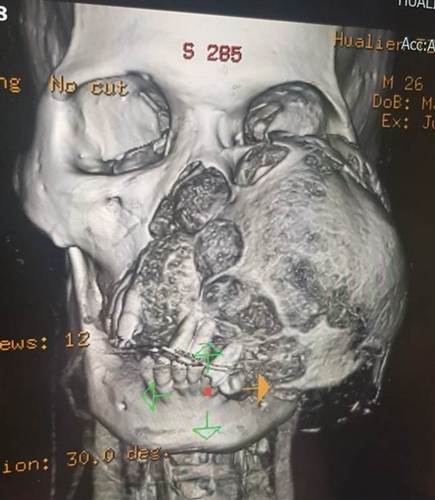

腫瘤影響的範圍太大每一刀都要特別謹慎,耳鼻喉科團隊以新技術克服出血問題取出12公分的巨型腫瘤,陳培榕副院長表示,雖然麥可腫瘤是良性的,但是腫瘤已侵犯顏面的骨頭,甚至從左側上顎鼻竇已經侵犯到鼻中膈,如果腫瘤不完全切除,一定會再復發,但是因為它的位置非常深且血流豐富,造成眼底及向外側顴骨破壞,同時左眼下方眼眶骨也被腫瘤擠壓,幸好腫瘤相當完整,且移除順利。接著由整形外科接力,為麥可進行眼眶顴骨複合區結構重建,重建被腫瘤吃掉的顴骨、上顎鼻竇與上顎齒槽骨,首次手術時間就長達十九個小時。

大破壞後的重建,要維持左眼、鼻部呼吸、口腔功能和外觀外,如何拼湊被腫瘤吃掉留下巨大傷口,才是整個手術的關鍵。主治醫師李俊達主任補充:「重建的步驟,是取小腿的腓骨與肌肉,補麥可的下眼眶與上顎位置,因為眼眶顴骨複合區的骨頭都被腫瘤吃掉了所以沒得支撐,要加上骨板固定下眼眶外;為配合上顎齒槽骨的形狀,整形外科團隊將筆直的小腿腓骨切成三段,折成彎曲的形狀,彎曲分裂處就用骨釘、骨板做銜接,讓上下牙齦的咬合能正常吻合。」

由於臉部肌肉、神經與血管構造相當複雜,手術時的重建復位工作必須非常精準。整形外科團隊將取下的腓骨細細拼湊,以顏面骨專用的骨釘、骨板固定復位後,連同皮瓣上的血管,以微創手術,與原部位的血管接合打通。這也是整個手術中,最複雜且耗時的部分。李俊達主任說:「血管的部分,則用腿骨血管接到頸部血管,兩邊都要接住,能吻合,不會漏血,也不會栓塞,整個皮瓣、骨頭才可以活,手術才算成功。」